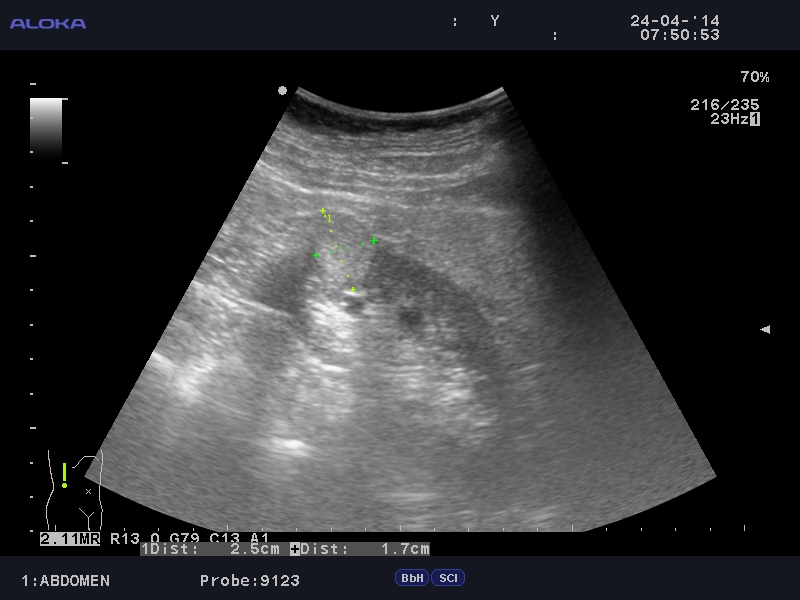

Онкоцитома почки - УЗИ

Женщина 76 лет. Жалоб не предъявляет.

t6_20140424_ABDOMEN_0002.JPG